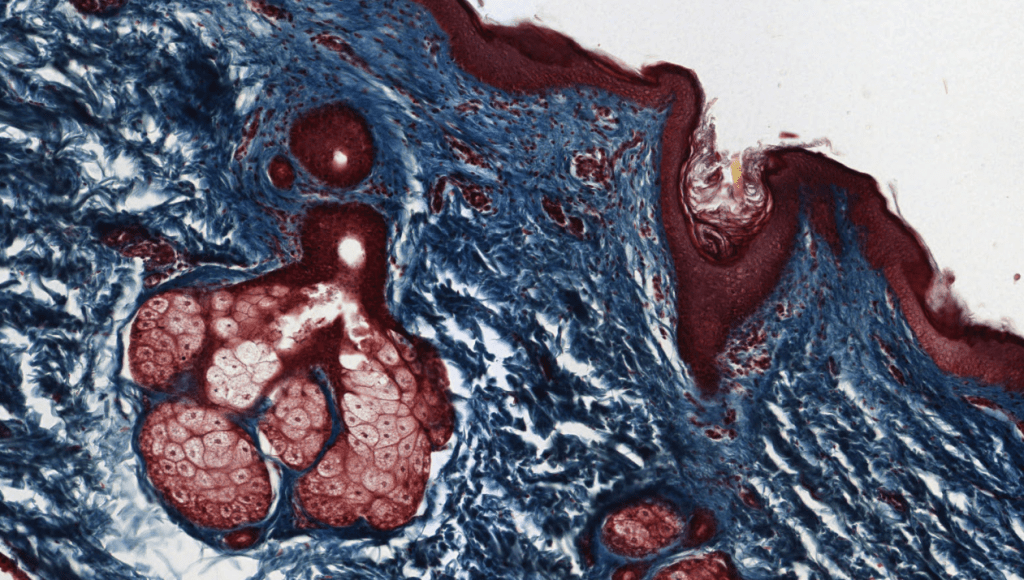

SEBÁCEAS

Su mecanismo de secreción es holocrino.

Asociadas a folículos pilosos.

Su secreción principal es sebo y este desaperec durante la técnica histológica, por eso se ve «pálido» con HyE.

Se ubican en casi toda la piel excepto piel gruesa.